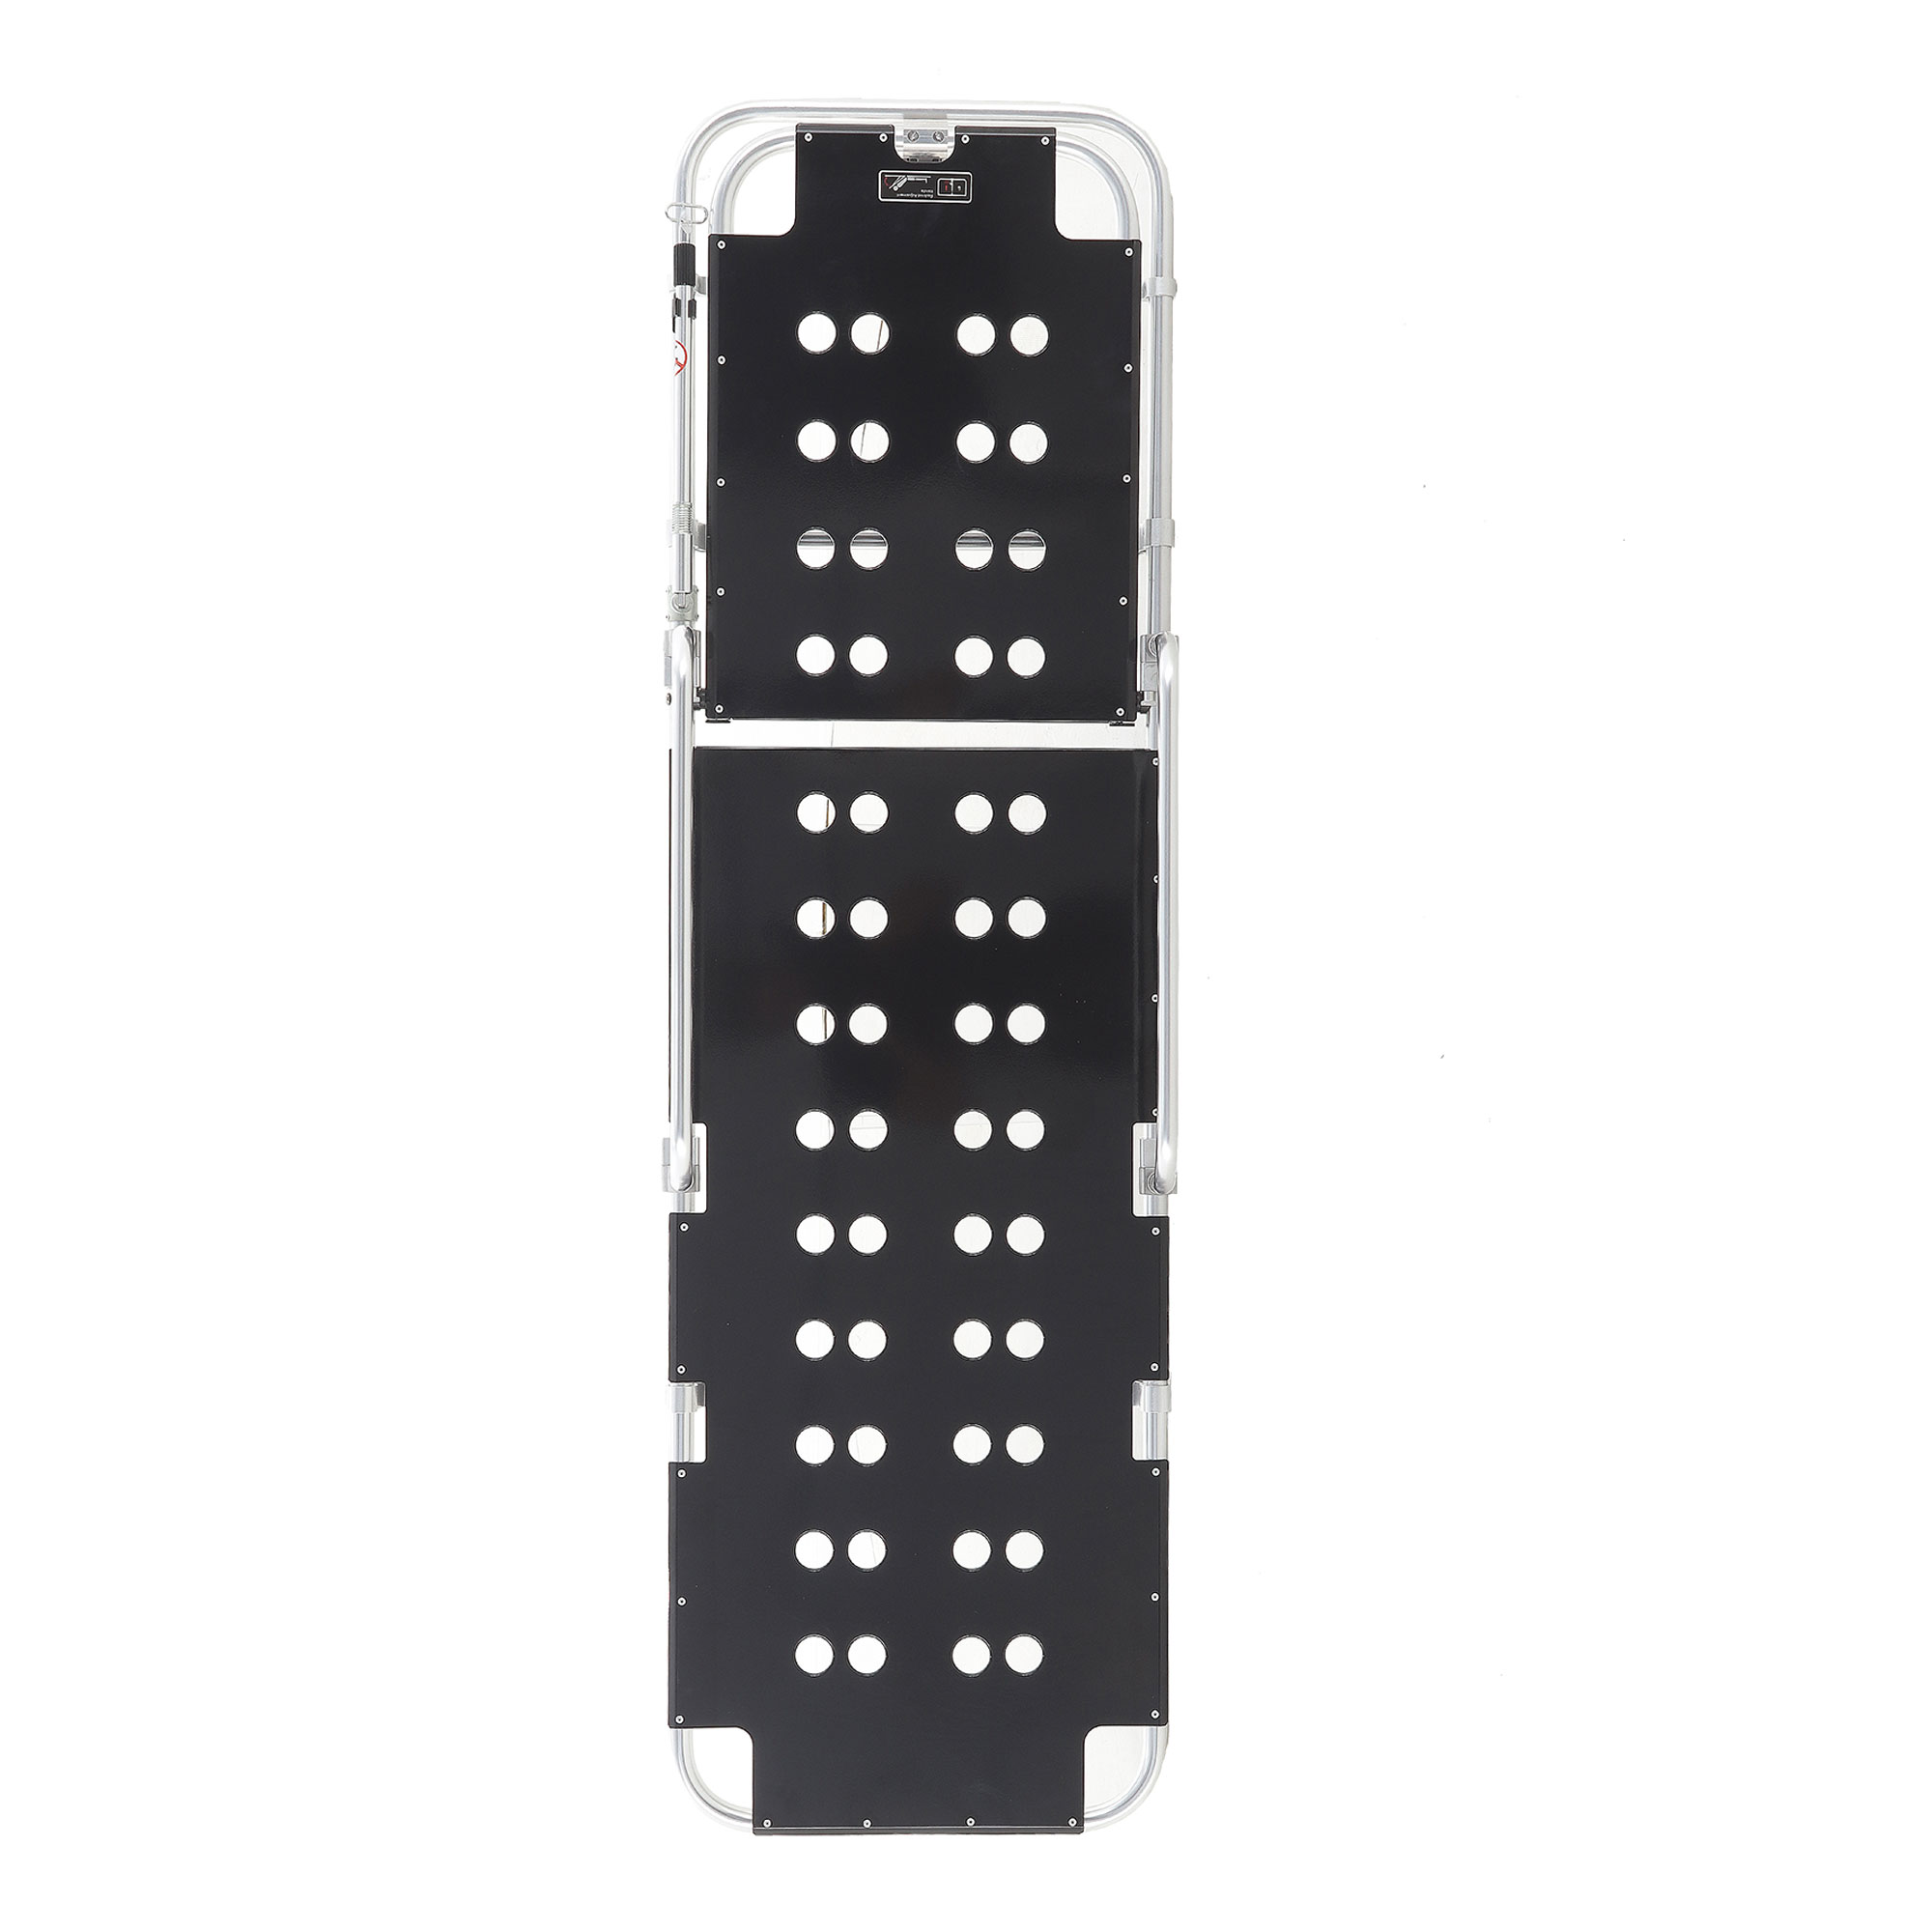

Тип каталки: |

Каркас: |

Вес: |

Нагрузка: |

Угол наклона головной секции: |

Инфузионная стойка: |

Разложенное состояние: |

Сложенное состояние: |